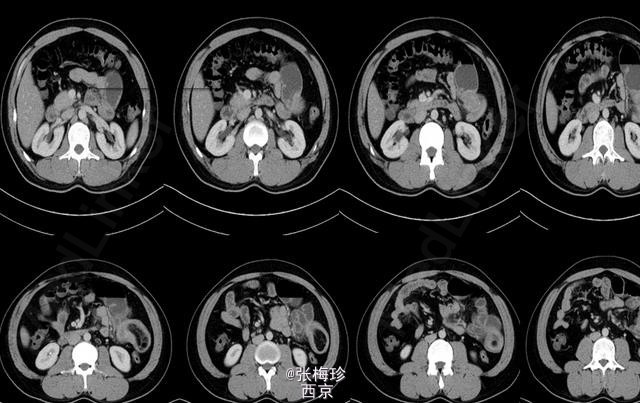

临床一例Meckel憩室

患者男性,30岁,2周前无明显诱因出现肚脐周围闷痛为绞痛伴恶心。

Meckel憩室 处理;手术治疗,解除梗阻并切除憩室

Meckel憩室及其并发症并无特殊的临床表现,与其他急腹症很难鉴别